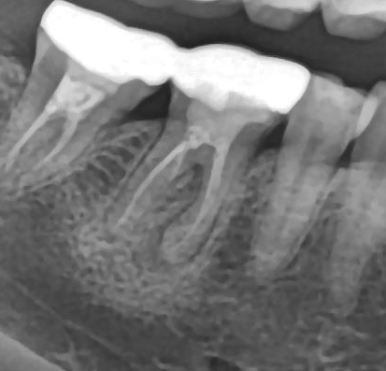

🦷 1. 치근단염 (치아 뿌리 염증)

- 원인: 충치, 외상 등으로 신경이 괴사된 경우

- 증상: 씹을 때 압통, 뿌리 쪽 묵직한 통증

- 치료:

- 신경치료(근관치료)

- 염증이 심하면 발치 필요